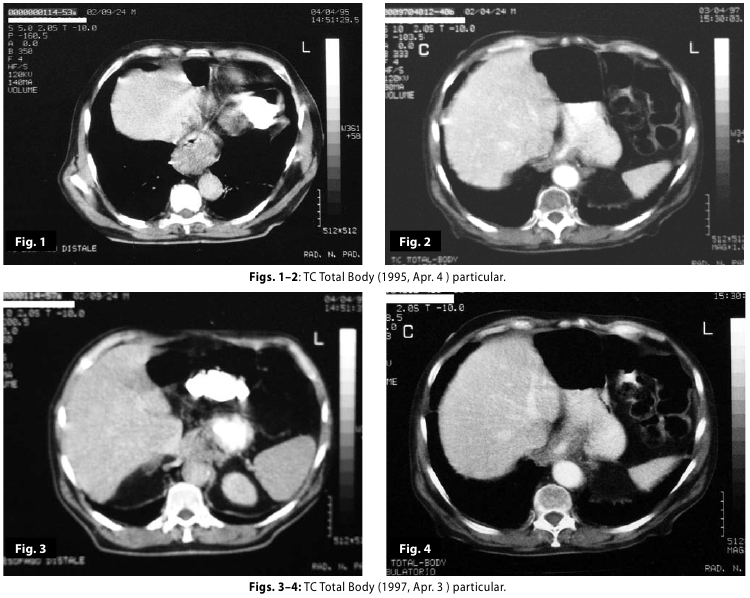

Figure1

Figure2

Figure1-2

Figure3

Figure4

Figure3-4

Figure1-2-3-4